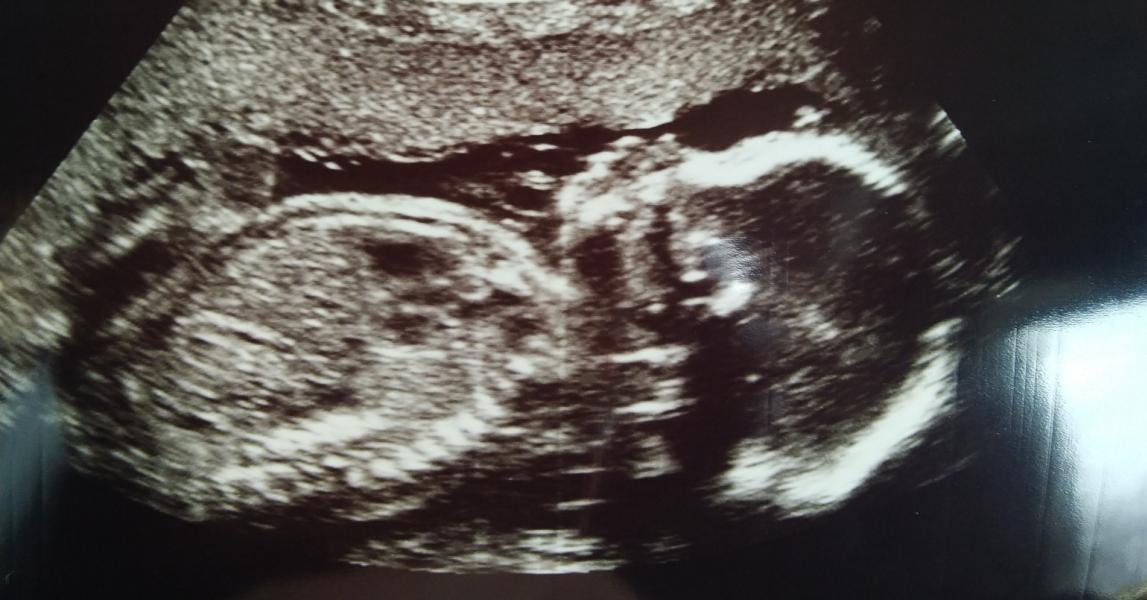

Подтвердили девчушку нам!!! Ура, чувствую будет драка с папой за имя🤣🤣🤣🤣

Поздравляю!))))))) 💐 второй скрининг самый классный) уже и поспокойнее идёшь на него и пол узнаешь)))